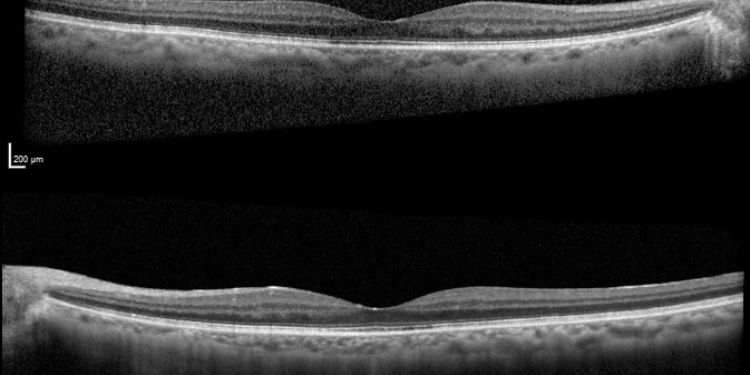

Leflunomide-Induced Cystoid Macular Edema: A Rare Case Report